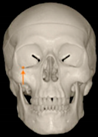

Three points determined the Acta plane: O, F right (FR), and F left (FL) (Table 2). Point O is the midpoint between the most craniodorsal point of the dorsum Sella and the most posterior dorsal point of the Basion in the midsagittal plane (Figure 1). Both points F are a result of the intersection between two lines: the line that connects the most inferior points of the lower orbital margins, right and left, and a line perpendicular to this line that runs through the most external points of the orbital margins, right and left (Figure 2). The new transverse reference plane, the Acta plane (Figure 2), is created by connecting the O-point (Figure 1) with FR and FL (Figure 2).

Figure 2.

(A) Construction of the F-points (right and left), frontal view. The F-points are originated from the intersection between the line connecting points A (the most inferior point of the lower orbit) and the perpendicular line to it that passes through points B (most external/lateral point of the Orbita). (B) Transverse view of the ACTA plane.